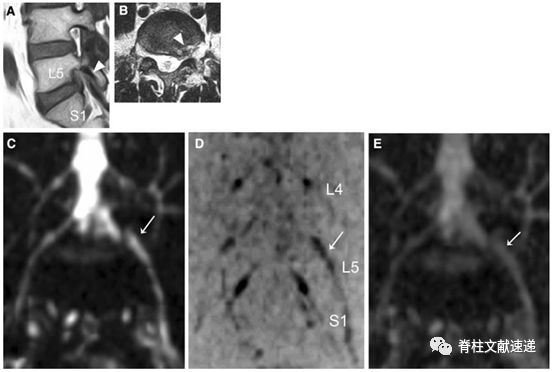

图注:47岁患者,L5/S1椎间盘突出。箭头显示L5椎间孔狭窄,神经周围脂肪信号消失。B图T2加权像,箭头显示孔内左侧椎间盘突出。E根据冠状面计算ADC图。箭头所示为神经根肿胀和凹陷。